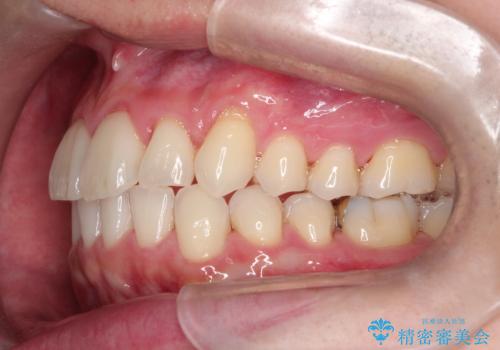

- 前歯の凸凹と顎の偏位を主訴に来院されました。

下顎の偏位を認めましたが、外科矯正を希望されなかったためできる範囲で顎の偏位を治すことができるよう治療を行なっております。

治療開始前に、下顎位の評価をおこなうことで、完成度の高い治療を行うことができました。